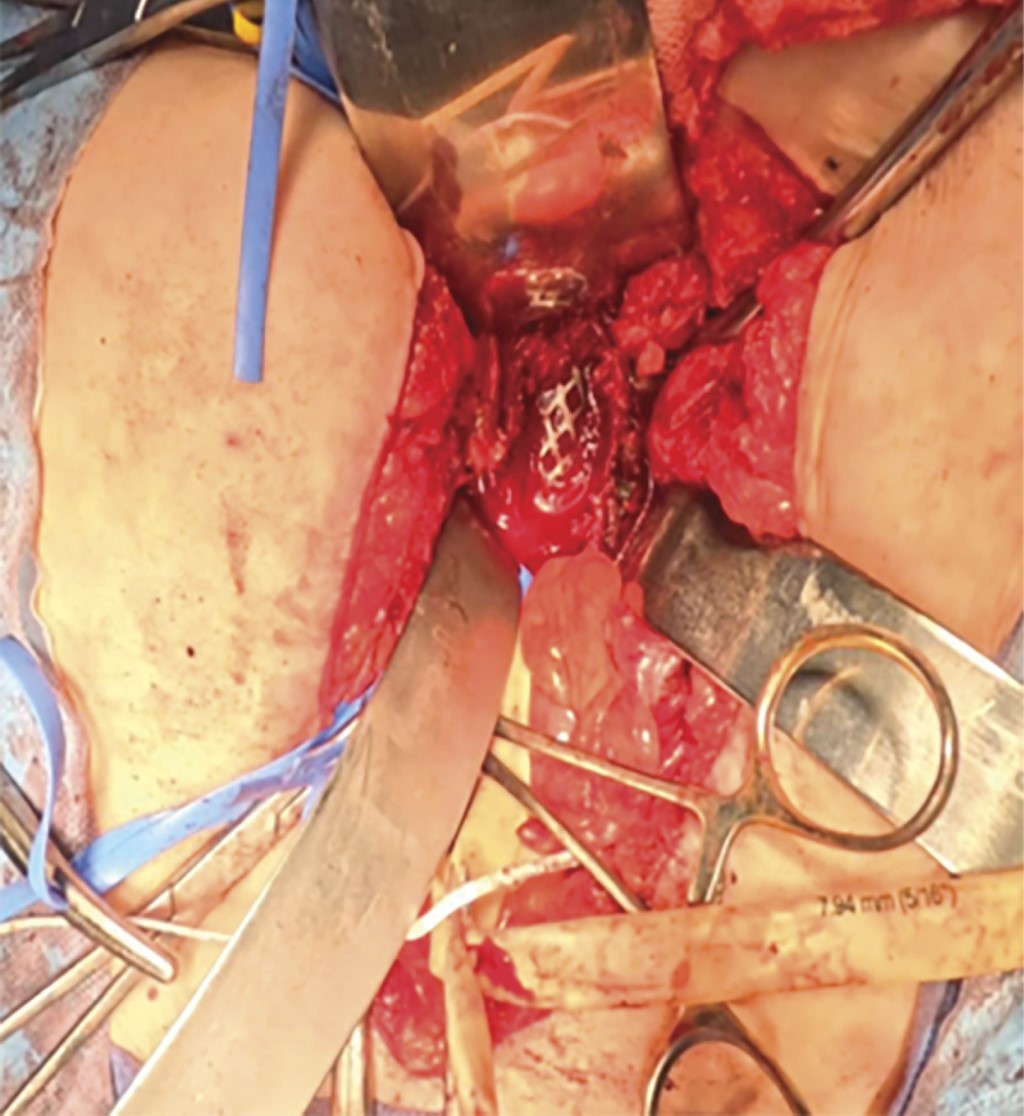

Recibimos paciente en consultorio con facies claras de dolor, sin tolerar la deambulación ni la sedestación, fuerza muscular para ambos miembros pélvicos 3/5 en todos los grupos musculares interferida por la generación de dolor a la movilización. Refiere adecuado control de esfínteres. Se solicitan radiografías en doble proyección como método de diagnóstico inicial, en donde se observa lesión en cuerpo vertebral L5, con aparente destrucción del mismo, por lo que se decide complementar el protocolo de estudio mediante serie ósea metastásica, tomografía axial computarizada (TAC) abdominopélvica y de columna-tórax y resonancia magnética simple de columna. A la revisión de la TAC de columna se observa la presencia de lesión lítica de quinto cuerpo vertebral lumbar, con afectación del muro posterior (Figura 1). En la resonancia magnética se describe la existencia de lesiones hiperintensas en L5 ocasionando compresión e invasión hacia canal medular de aproximadamente 70%. Considerando el aumento de la sintomatología más el grado de compresión, se considera realizar tratamiento quirúrgico consistente en descompresión mediante lumbotomía de L5 por abordaje anterior más colocación de malla con injerto autólogo e instrumentación transpedicular L3-S1 con aumento a iliacos y envío de la muestra obtenida por corpectomía a patología y cultivo (Figura 2). Se obtienen resultados de patología a las dos semanas posteriores, en donde se reporta muestra macroscópica compatible con carcinoma folicular de tiroides, motivo por el cual se solicita valoración por servicio de oncología y oncocirugía, en donde se realiza como complemento de estudio ultrasonido Doppler de tiroides objetivándose presencia de nódulos tiroideos, por lo que se inicia protocolo quirúrgico para realización de tiroidectomía total. Después de ambos procedimientos quirúrgicos, la paciente muestra adecuada evolución clínica sin datos de proceso infeccioso agregado iniciando deambulación progresiva y con seguimiento por medio de la consulta externa por servicios correspondientes (Figura 3).